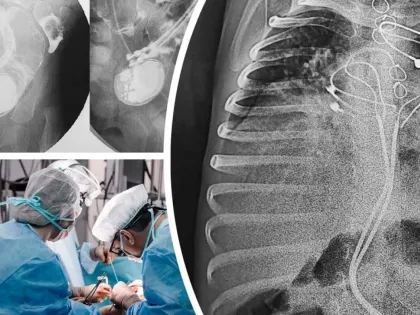

В Новосибирске хирурги спасли 3-летнего ребенка с кардиостимулятором в кишечнике

В Новосибирске произошел редкий клинический случай Хирурги клиники Мешалкина и Новосибирской областной больницы спасли 3-летнего ребенка с кардиостимулятором в кишечнике.